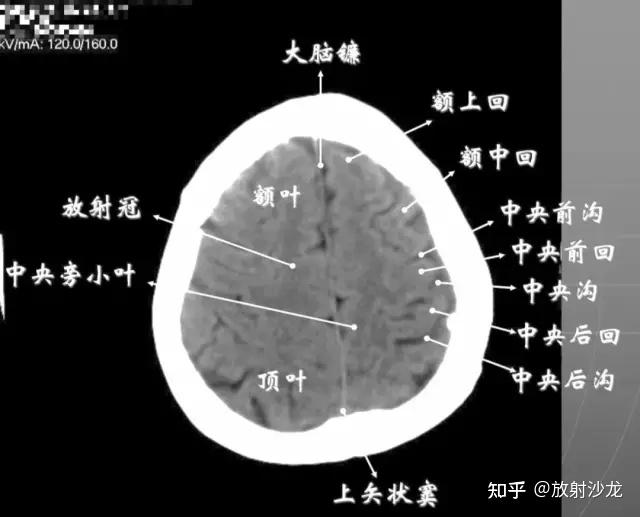

头颅ct 解剖图谱,人手一份

颅脑ct解剖

头部ct影像解剖